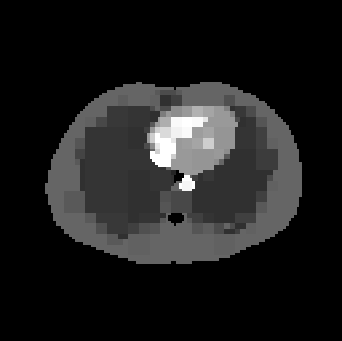

An alternative to the 1subscript1\ell_{1}- and TV-norm penalties can be formulated using model-based estimates that utilize structure in the coefficients beyond that of a sparse representation. In particular, we build upon the framework of recursive dyadic partitions (RDP), which we summarize here and are described in detail in [willett:density]. Let 𝒫𝒫\mathcal{P} be the class of all recursive dyadic partitions of [0,1]2superscript012[0,1]^{2} where each cell in the partition has a sidelength at least 1/n1𝑛1/\sqrt{n}, and let P𝒫𝑃𝒫P\in\mathcal{P} be a candidate partition. The intensity on P𝑃P, denoted f(P)𝑓𝑃f(P), is calculated using a nonnegative least-squares method to fit a model (such as a constant) to sksuperscript𝑠𝑘s^{k} in (15) in each cell in the RDP. As an example, consider Fig. 1. Here we approximate the true image (Fig. 1(a)) on the recursive dyadic partition defined in Fig. 1(b)). The result is a piecewise constant approximation to the emission image (Fig. 1(c)). We see that the partition model is able to accurately capture the image in clear multiresolution fashion: large homogeneous regions are well-modeled by large cells, whereas edges are approximated via the deeper recursive partitioning. Furthermore, a penalty can be assigned to the resulting estimator which is proportional to |P|𝑃|P|, the number of cells in P𝑃P. Thus we set

Refer to caption

Figure 1: Example of a partition-based approximation. (a) True image. (b) Recursive dyadic partition (RDP). (c) RDP-based approximation of the true image.